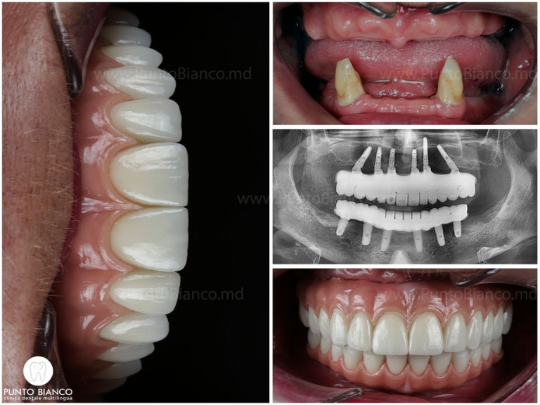

«Мы — одна из немногих стоматологических клиник Молдовы, которая не только обещает, но и действительно выполняет установку имплантов и фиксирует временные зубы уже в день операции или на следующий день. Это стало возможным благодаря современным технологиям, которыми оснащена клиника Punto Bianco (цифровые оттиски, выполненные с помощью самого современного интраорального сканера, 3D-томография прямо в клинике, собственная цифровая лаборатория), а также мультидисциплинарной команде с большим опытом в полном и сложном восстановлении зубных рядов.»